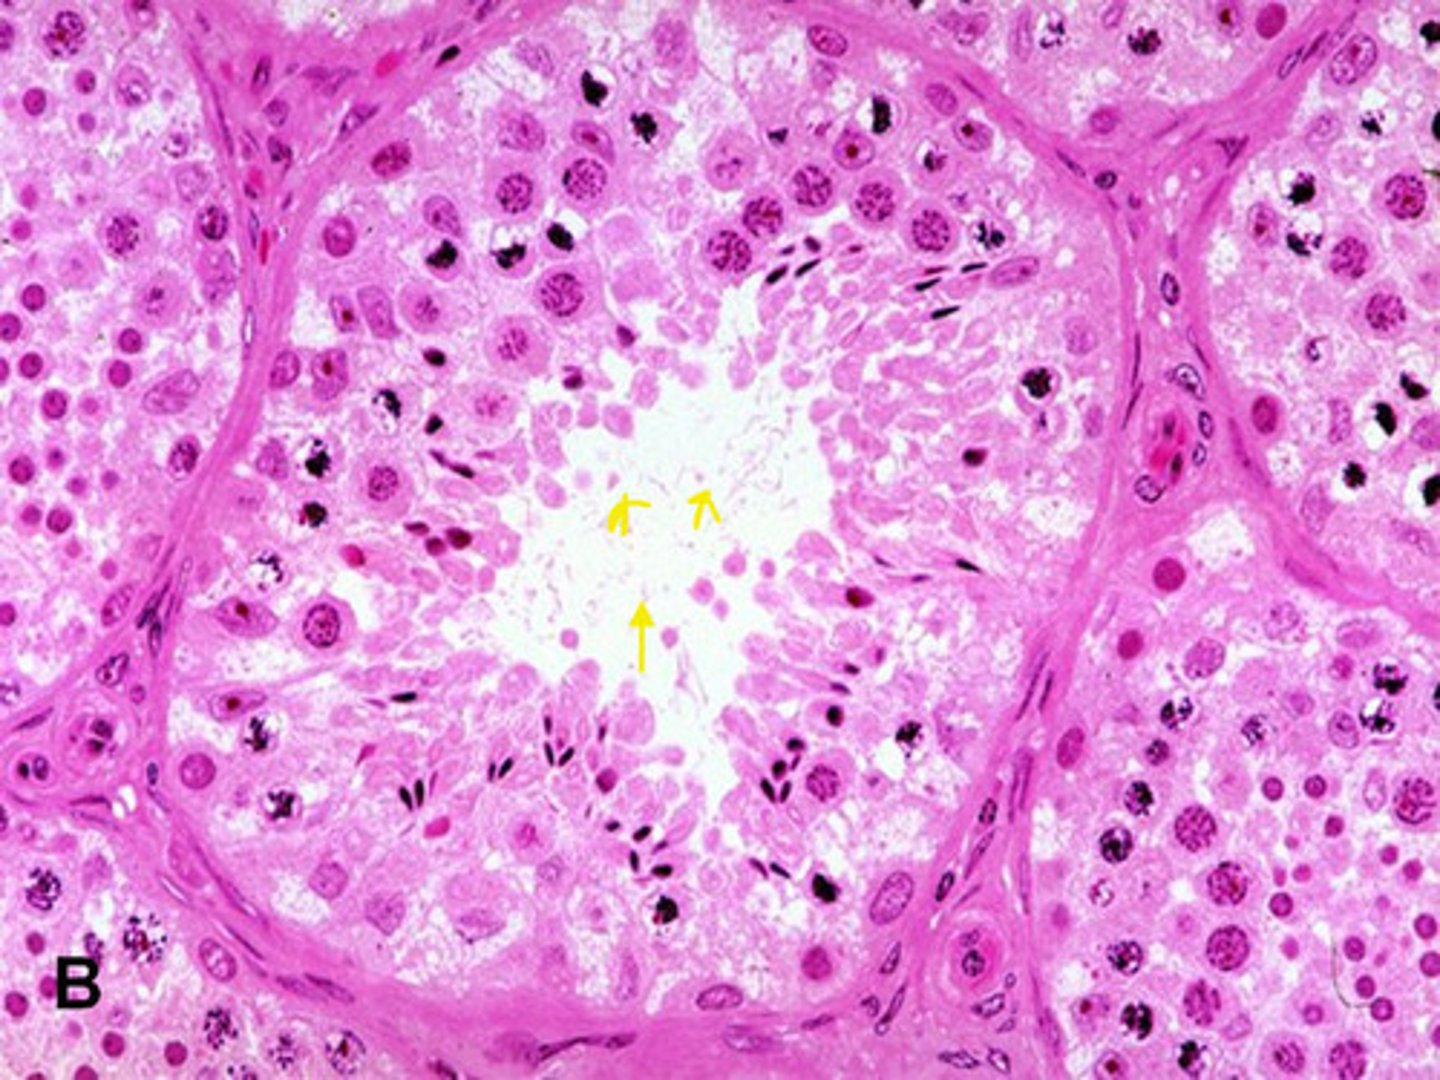

seminiferous tubule of testis

interstitial cells of leydig of testis

sperm cells of testis